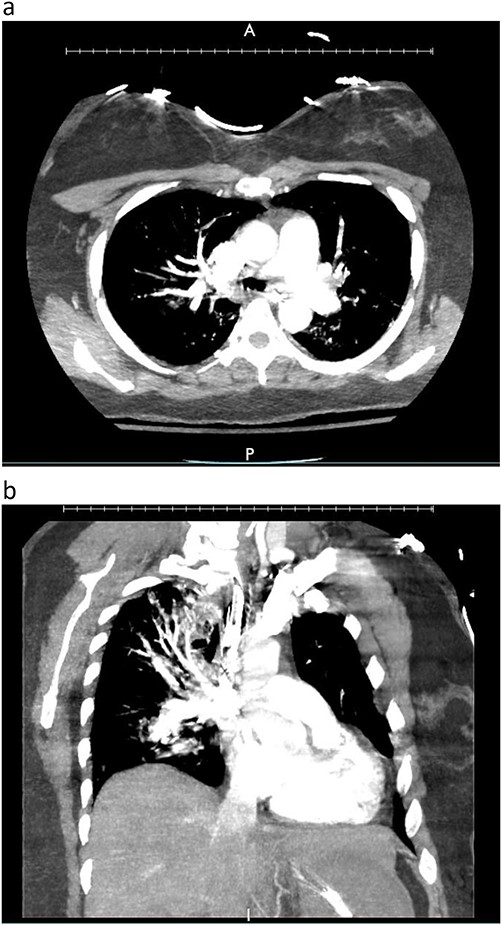

A woman in her mid-30s had hypoxic brain injury after cardiac arrest from drug overdose and was declared brain dead 4 days after hospitalization. PaO2 was 466 mm Hg with a fraction of inspired oxygen of 1.0 and positive end-expiratory pressure of 5 cm H2O. Chest computed tomography (CT) angiography showed a subtle filling defect in the left pulmonary artery (LPA) (Fig. 1). Intraoperative bronchoscopic findings were unremarkable. On visual inspection, the lungs appeared normal and had adequate compliance. We accepted and procured the lungs en bloc. Retrograde flushing evacuated several small clots from the pulmonary arteries. Both lungs were packed and transported as usual.

Donor angio CT scan: (a) filling in the left PA, (b) reduction of blood supply of the left lung.